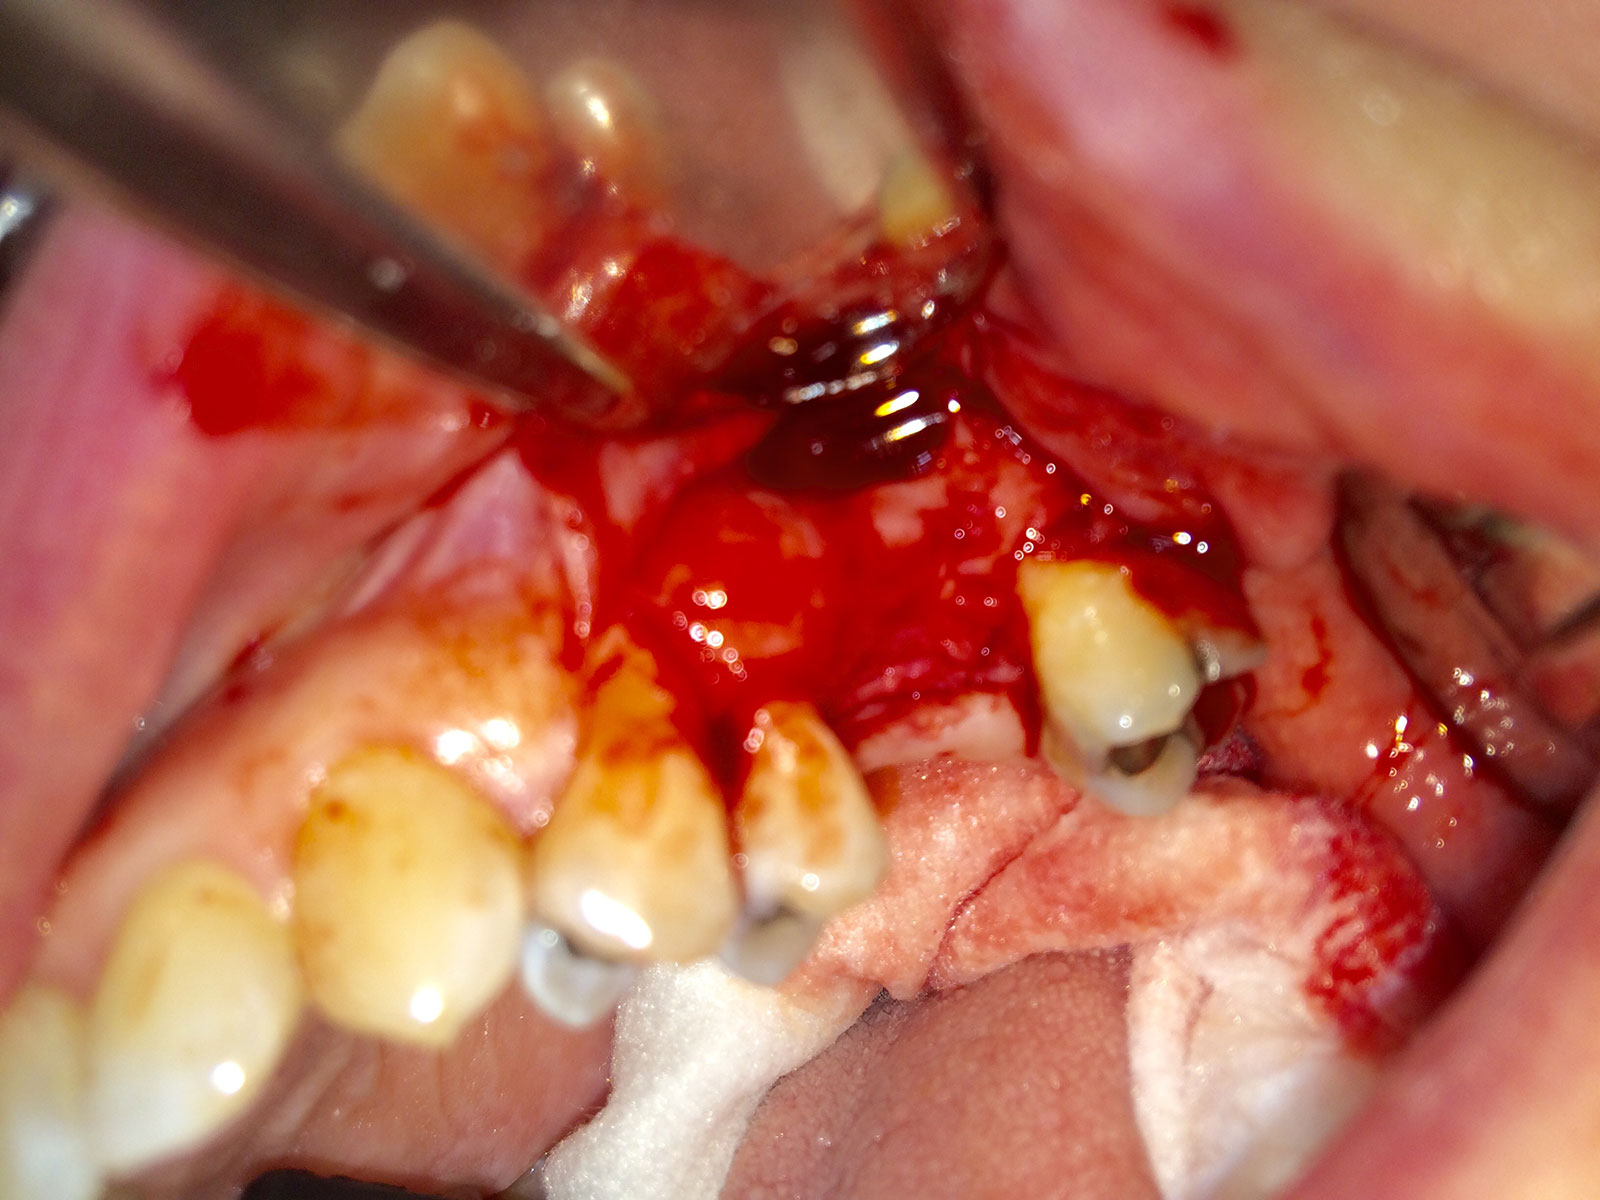

Sinus Grafting Procedures

A sinus grafting procedure, also known as a sinus augmentation, is for patients who have insufficient natural bone in the areas where dental implants are needed. They are long lasting, strong and sturdy, and fit and function like natural teeth. The procedure involves adding bone, either your own natural bone from another part of the body, from a donor or made of processed or synthetic bone material, and placing it below the sinus so that the implants can be placed. After the bone has healed and developed, usually around four to 12 months, the dental implants can be placed.

The photos on this website are from real surgeries performed by Dr. Ulloa. Due to the

graphic nature of the images and content, viewer discretion is advised.